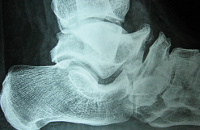

Ακτινολογικά σχεδόν πάντα υπάρχουν ευρήματα όπως:

1. Οστικές γέφυρες του ταρσού,

2. Κατάγματα της περιοχής,

3. Κάθετη θέση του αστραγάλου.